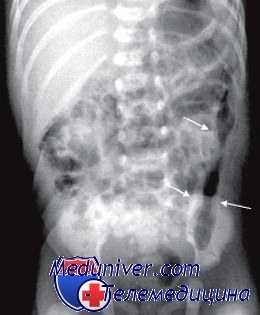

Толстокишечная непроходимость

г) Болезнь Гиршпрунга. Сужение прямой и сигмовидной кишок; расширение проксимальных отделов толстой кишки.

Обычно болезнь Гиршпрунга наблюдается как изолированный порок развития, по у 10% больных имеется трисомия 21-й хромосомы. У новорожденных с болезнью Гиршпрунга наблюдается нарастающее вздутие живота, рвота, замедленное отхождение мекония или его отсутствие в первые 48 часов жизни. В более старшем возрасте характерны постоянные запоры, вздутие живота, истощение. Объективный осмотр выявляет только резкое вздутие живота. Рентгенологические данные указывают на низкую кишечную непроходимость. Ирригоскопия облегчает диагноз.

Так как болезнь Гиршпрунга поражает наиболее дистальные отделы толстой кишки всегда, а проксимальные — в различной степени, при ирригоскопии выявляется спастическое сокращение прямой и сигмовидной кишок и расширение проксимальных отделов толстой кишки. В пользу диагноза болезни Гиршпрунга свидетельствует замедленная (более 24 часов) эвакуация контрастного вещества. Аганглиоз, выявленный при аспирационной биопсии прямой кишки, подтверждает диагноз. Хирургическая коррекция заключается в резекции пораженного аганглиозом сегмента (прямой кишки и дистальных отделов ободочной) с наложением анастомоза.